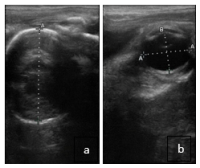

Ultrasounds later in pregnancy can help ensure the foal is in a normal position and act as a screening tool for placentitis—an inflammation of the placenta that can lead to late-term abortion, stillbirth, or premature birth. The process—a transrectal ultrasound—can be brief and non-invasive, while offering valuable information, says UC Davis.

A fetus will typically settle into its final presentation between 9 and 11 months of gestation. By identifying the fetal head or eye, an ultrasound can reveal if the foal is in a normal anterior presentation, with its head first, or if it is in an abnormal position.

Veterinarians may detect the foal’s tail, thighs, or spine during the ultrasound if the fetus is in an abnormal position, such as posterior (hindquarters first) or transverse (sideways). According to UC Davis, fetal malpresentation is not common, but when it does occur, it can lead to a difficult birth, called dystocia, which can put the mare and foal at risk.

In addition to helping detect malpresentation, late gestation ultrasounds can also screen for placentitis, which is the top cause of infectious abortion in mares.1 The condition, according to UC Davis, tends to develop close to the cervix, allowing veterinarians to detect it through a transrectal ultrasound. Mares with placentitis may exhibit thickening of the placenta or partial separation of the placenta from the uterus in the early stages.